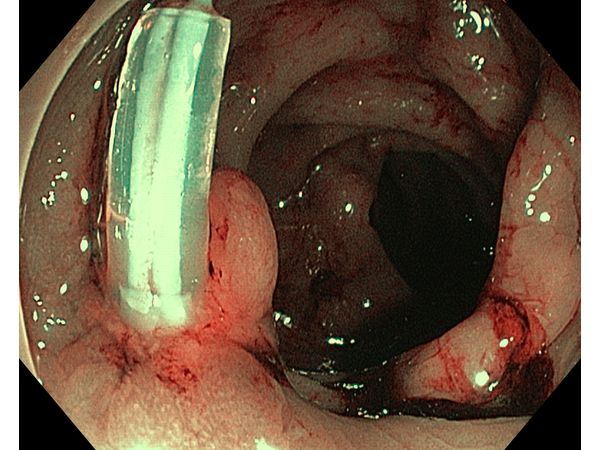

- тубуло-ворсинчатую аденому на ножке (0-Iр) размером 13 мм, в некоторых областях сосудистый рисунок был разрушен и не просматривался (NICE-3).

Новообразования вырезали сразу во время колоноскопии: первые три опухоли удалили с помощью холодной петли, а последнюю — с помощью горячей петли, предварительно наложив на ножку нейлоновую нить (EndoLoop).